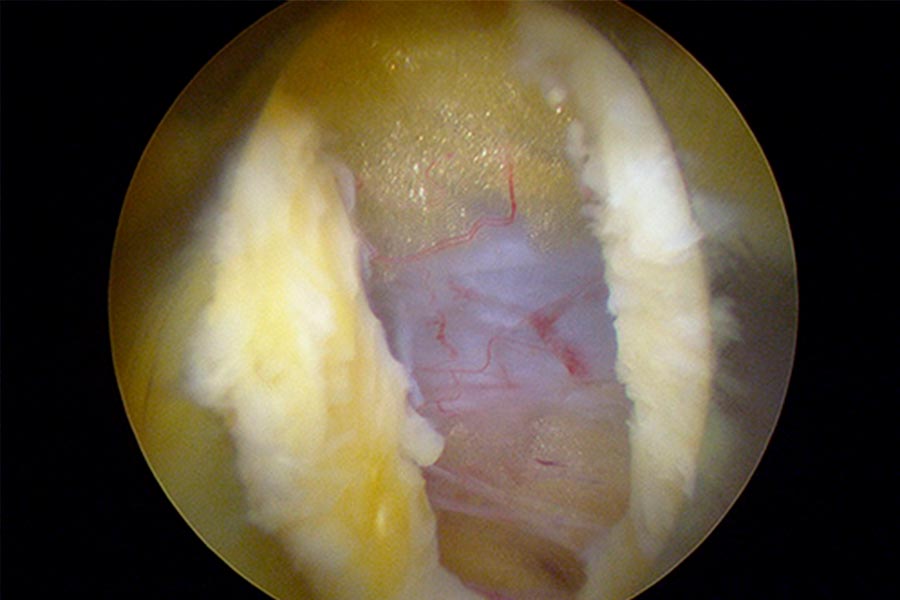

Durante la intervención quirúrgica, se abordarán los dos niveles mediante la técnica de endoscopia de columna.

Mediante una incisión mínima en la piel de 2-3 milímetros, el equipo de ICAC tratará a una paciente joven que sufre una una hernia discal en L4L5 y L5S1.

Tras una operación de columna, la paciente presenta una masa blanquecina que se decide retirar mediante técnica avanzada de endoscopia de columna